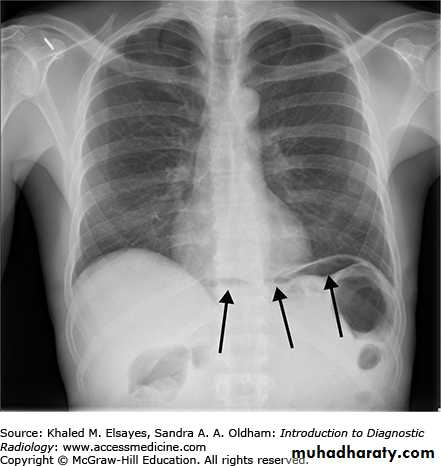

Chest x-ray may be abnormal in late dis., with widening of mediastinum (oesophageal dilatation) and presence of aspiration pneumonitis.Barium swallows . Tapered narrowing (bird beak) of the lower oesophagus and dilating body of oesophagus, a peristaltic and food filled (sigmoid oesophagus).

Chest x-ray and abdominal u\s to exclude metastatic lesion.